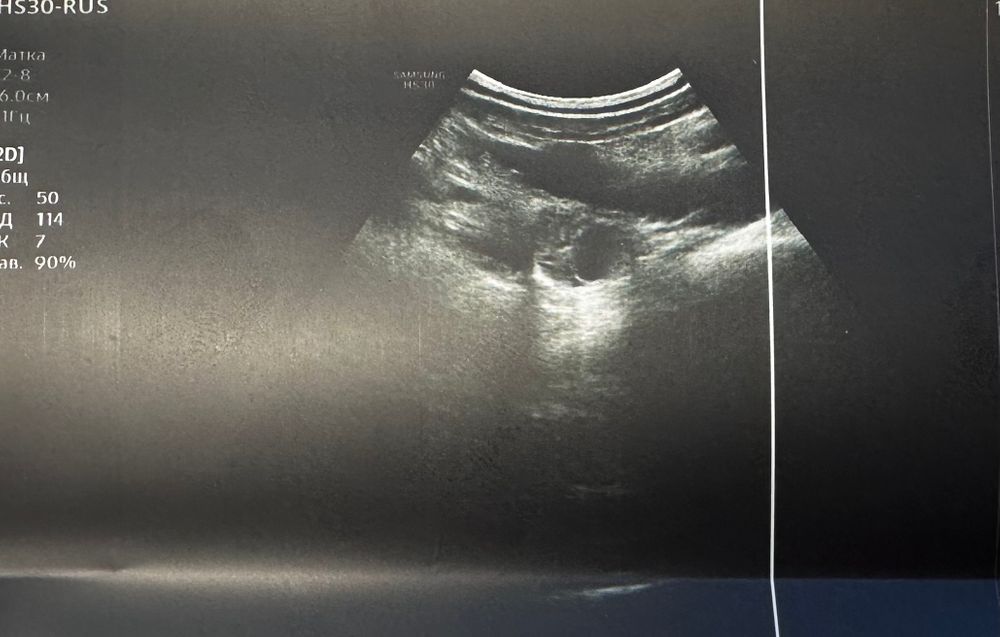

УЗИ на 16 день цикла

Всем привет! 16 дц, была на узи. Я правильно понимаю, что на одной фотографии- один яичник, а на другой- другой яичник с доминантным фолликулом?